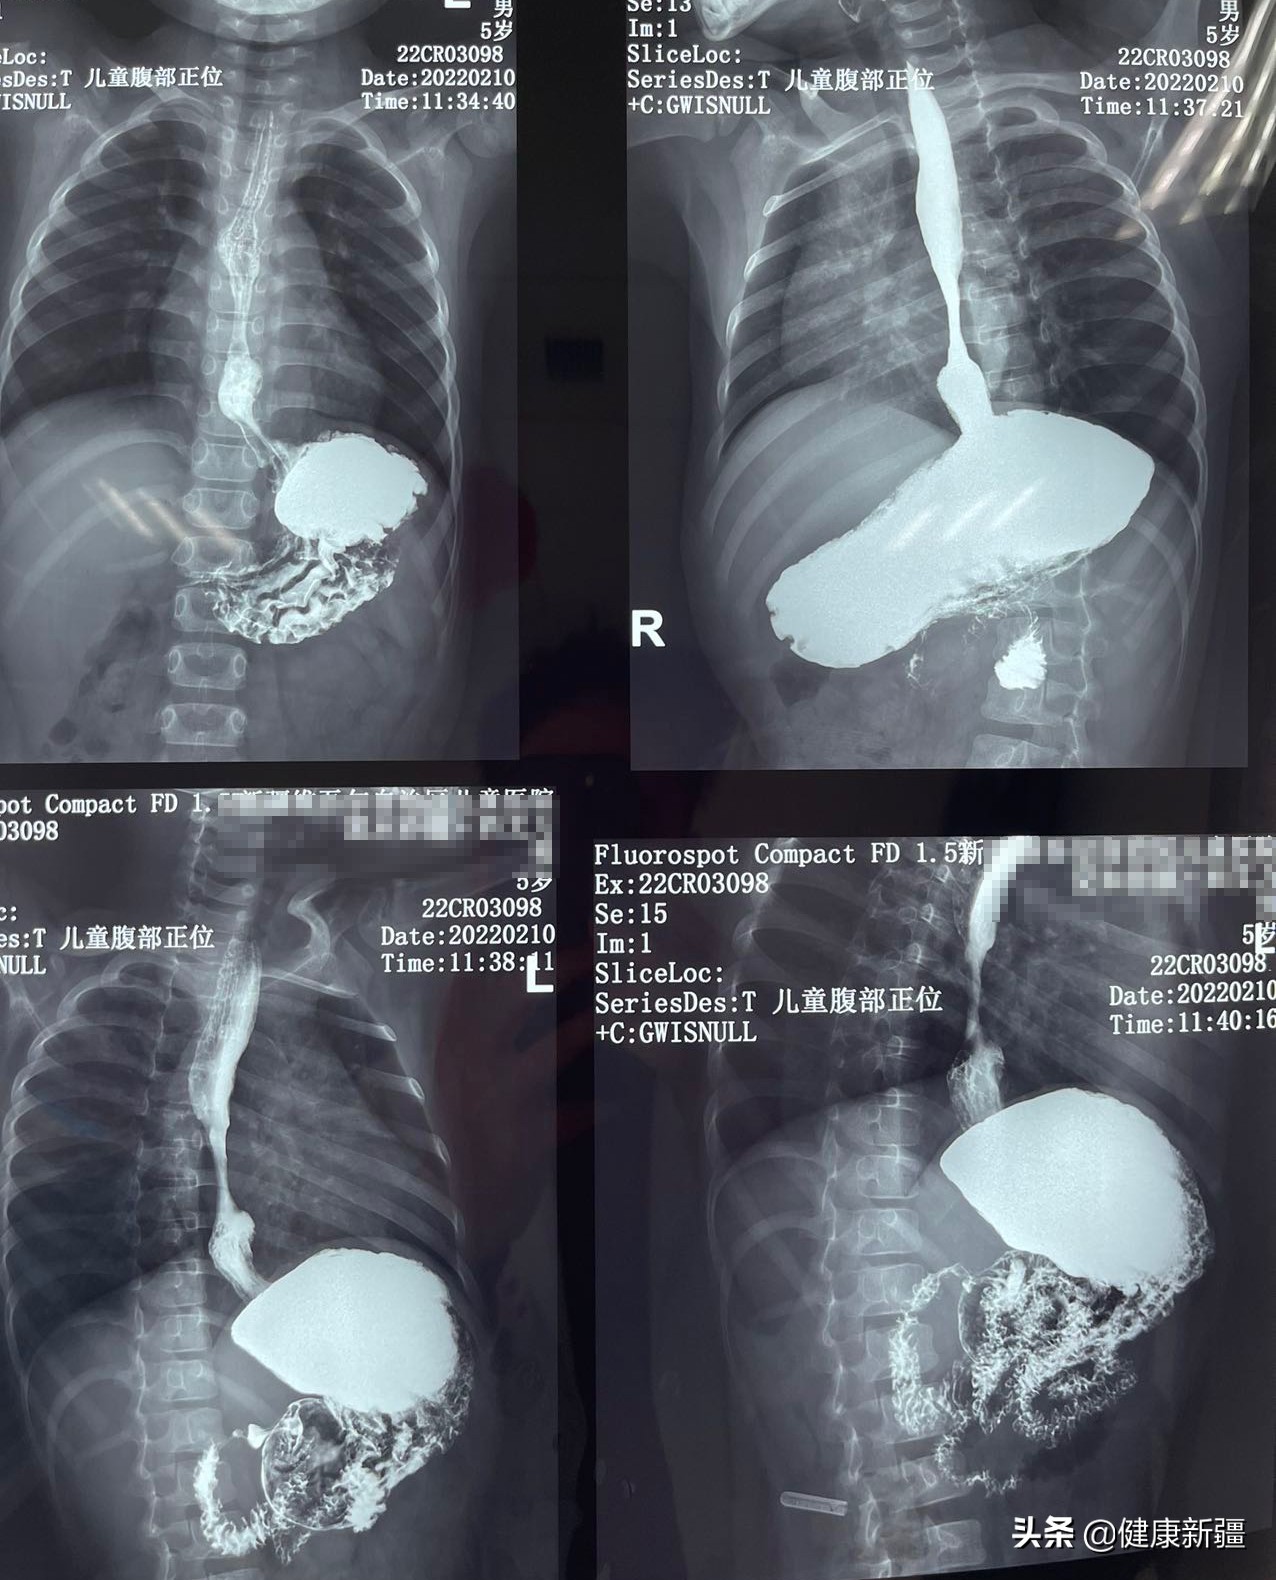

小夏木影像资料

“胃食管反流病很常见,婴幼儿由于先天发育不全等问题,也会出现胃食管反流。”北京儿童医院新疆医院普外科主任和军表示,由于胃食管反流严重,导致部分食管面反复溃疡,最终形成食管狭窄并发食管裂孔疝。经食管24小时pH监测仪监测显示,小夏木的胃食管反流值监测数值高达176.9(正常值≤14.7),且食管病理性反酸以直立位为主,这在婴幼儿中非常少见,“长期口服抑酸药物,又阻碍铁的吸收,所以小夏木又出现了重度贫血。”